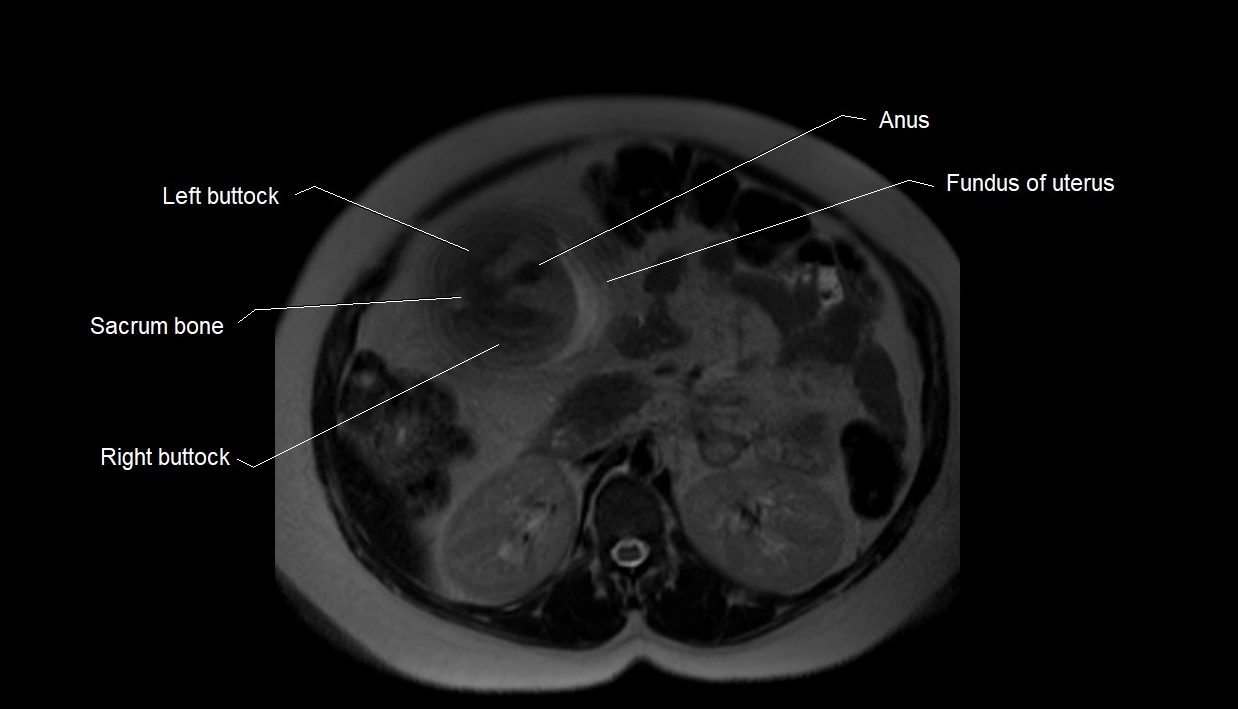

Relations

• Enclosed within the amniotic sac, bounded by the amnion and chorion

• Surrounds and cushions the developing fetus

• In continuity with maternal circulation through placental and transmembrane exchanges